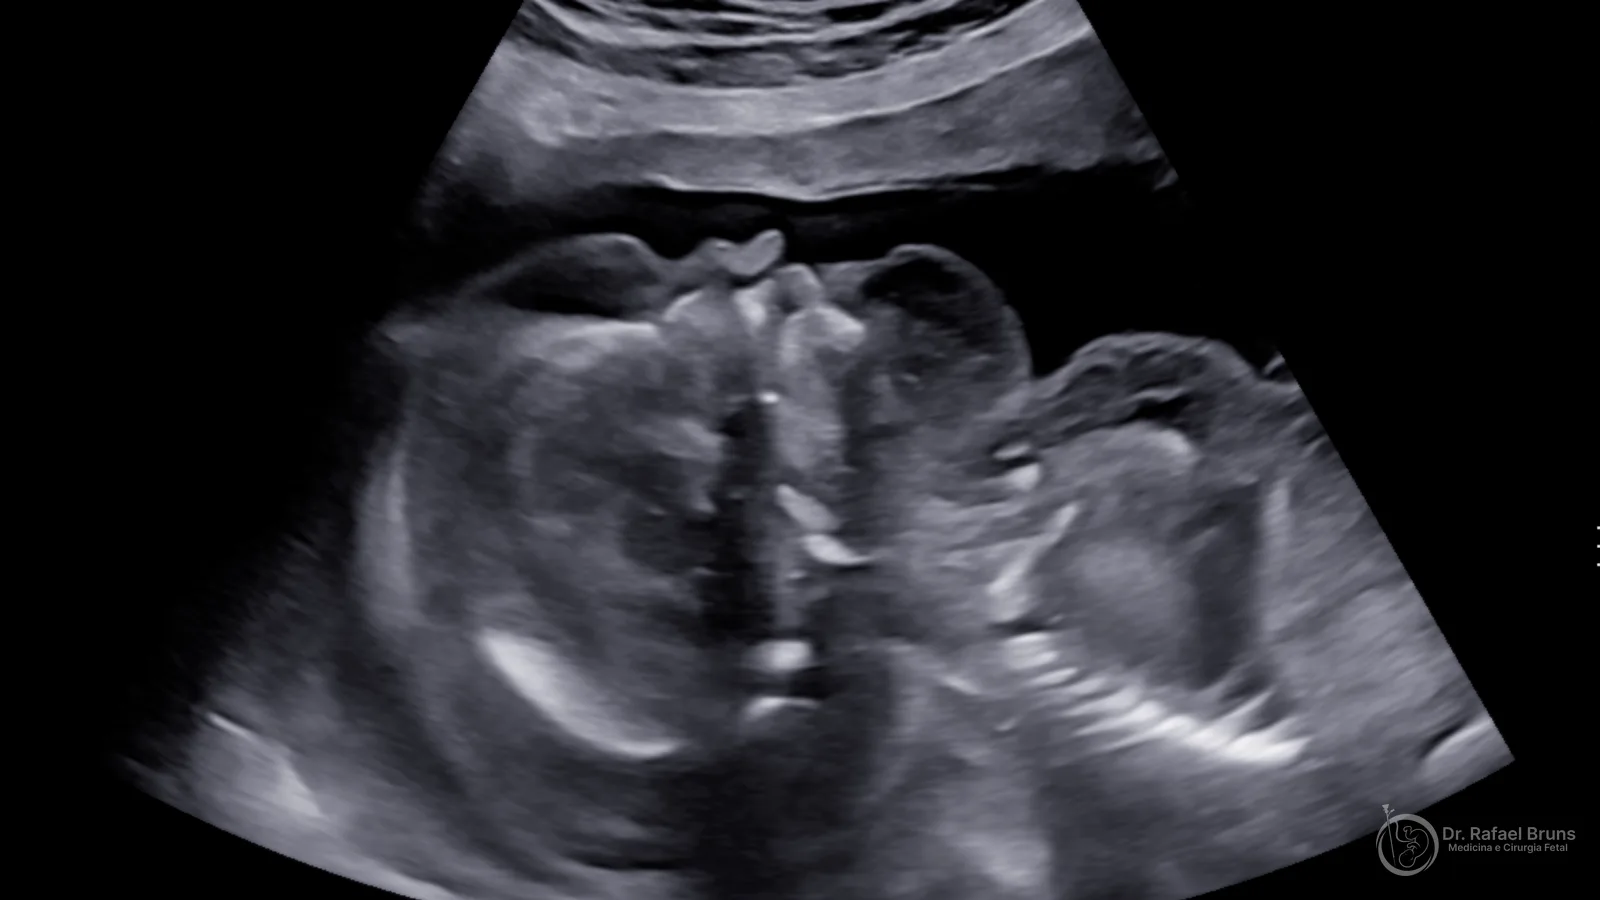

Hidropsia fetal é o acúmulo anormal de líquido em pelo menos dois compartimentos do corpo do bebê. Os locais mais comuns são a cavidade abdominal (ascite), ao redor dos pulmões (derrame pleural), ao redor do coração (derrame pericárdico) e sob a pele (edema subcutâneo). Em muitos casos, há também espessamento da placenta e aumento do líquido amniótico.

O diagnóstico é feito pelo ultrassom — muitas vezes durante a ultrassonografia morfológica do segundo trimestre, entre as semanas 18 e 22 da gestação. A ultrassonografia pré-natal identifica o acúmulo de líquido nos tecidos fetais e nas cavidades corporais, orientando a investigação das causas.

Ultrassom de feto hidrópico mostrando edema subcutâneo importante, derrame pleural e discreta ascite — acervo pessoal do Dr. Rafael Bruns, todos os direitos reservados.